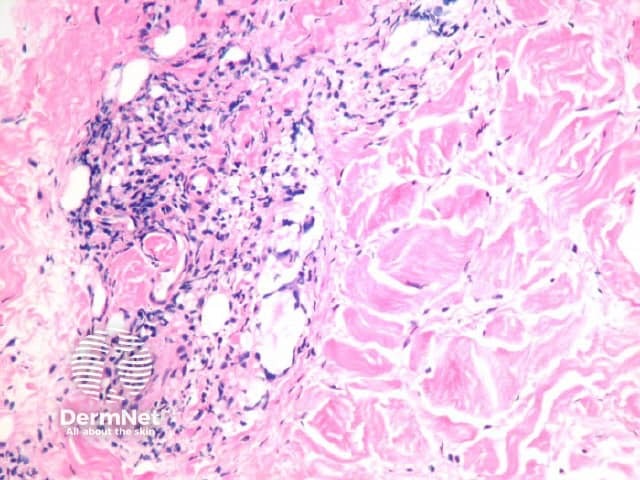

The yeast forms of cryptococcosis are usually surrounded by massive gelatinous oedema (figure 1, arrow). The surrounding inflammatory reaction depends on the stage of the clinical lesion and on the immune status of the patient. Immunocompetent patients may elicit a brisk granulomatous response in which the organisms may be difficult to see without special stains, while immunocompromised patients show minimal inflammation and oedema around the numerous yeast forms as seen in the case illustrated here (figure 2). The yeast forms of cryptococcosis are usually widely separated by their thick mucoid capsules. PAS stain decorates the yeasts (figure 3) and mucicarmine stain decorates the highly characteristic gelatinous capsule a bright pink (figure 4).

Figure 1

Figure 2